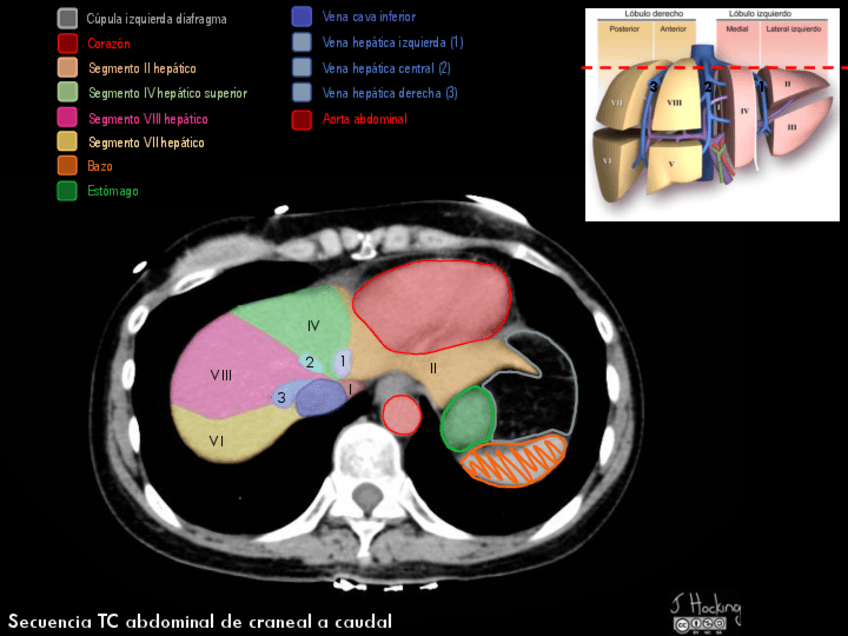

He publicado nuevos apuntes de Anatomía por la imagen: TCSegmentacion-hepatica-y-digestivo.pdf

28 páginas

He publicado nuevos apuntes de Anatomía por la imagen: Imagenes-TC-RM-abdominal.pdf

63 páginas

He publicado nuevos apuntes de Anatomía por la imagen: Aparato-DIGESTIVO.pdf

19 páginas